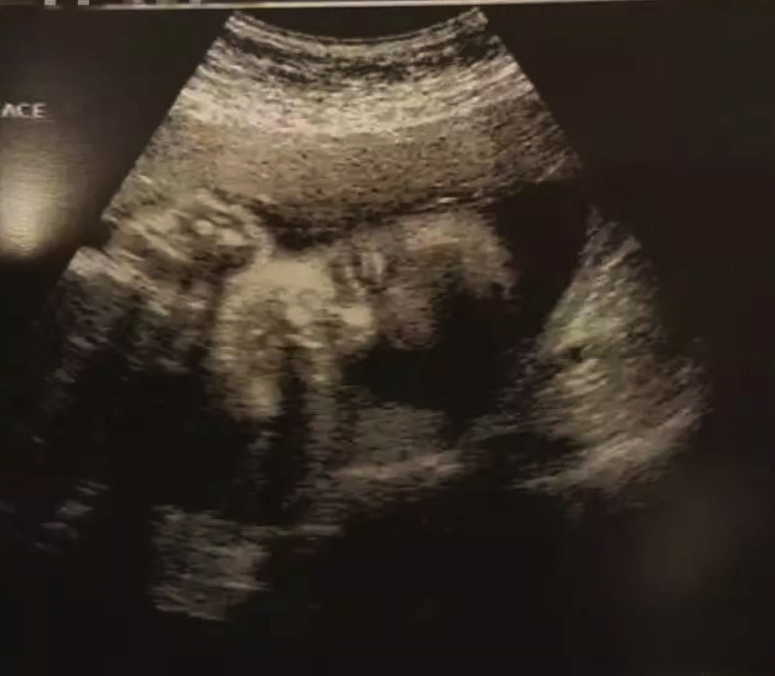

从2004年到2016年,我12年的奋战史终于成功了,为了呵护好腹中的孩子,我决定在美好好安胎,等三个月稳定后再回国。8月22日,我去诊所做了B超,医生微笑着告诉我,已有胎心搏动,想着腹中还有另外一个小人儿的心跳,我的内心就激动。原本以为这一生都不会怀孕,没成想,在多年的坚守后,我还能怀自己的孩子。并且,我的医生告诉我,怀孕和生产对于腺肌症是有好处的,我还要感谢我的孩子,为我驱走病痛的折磨。